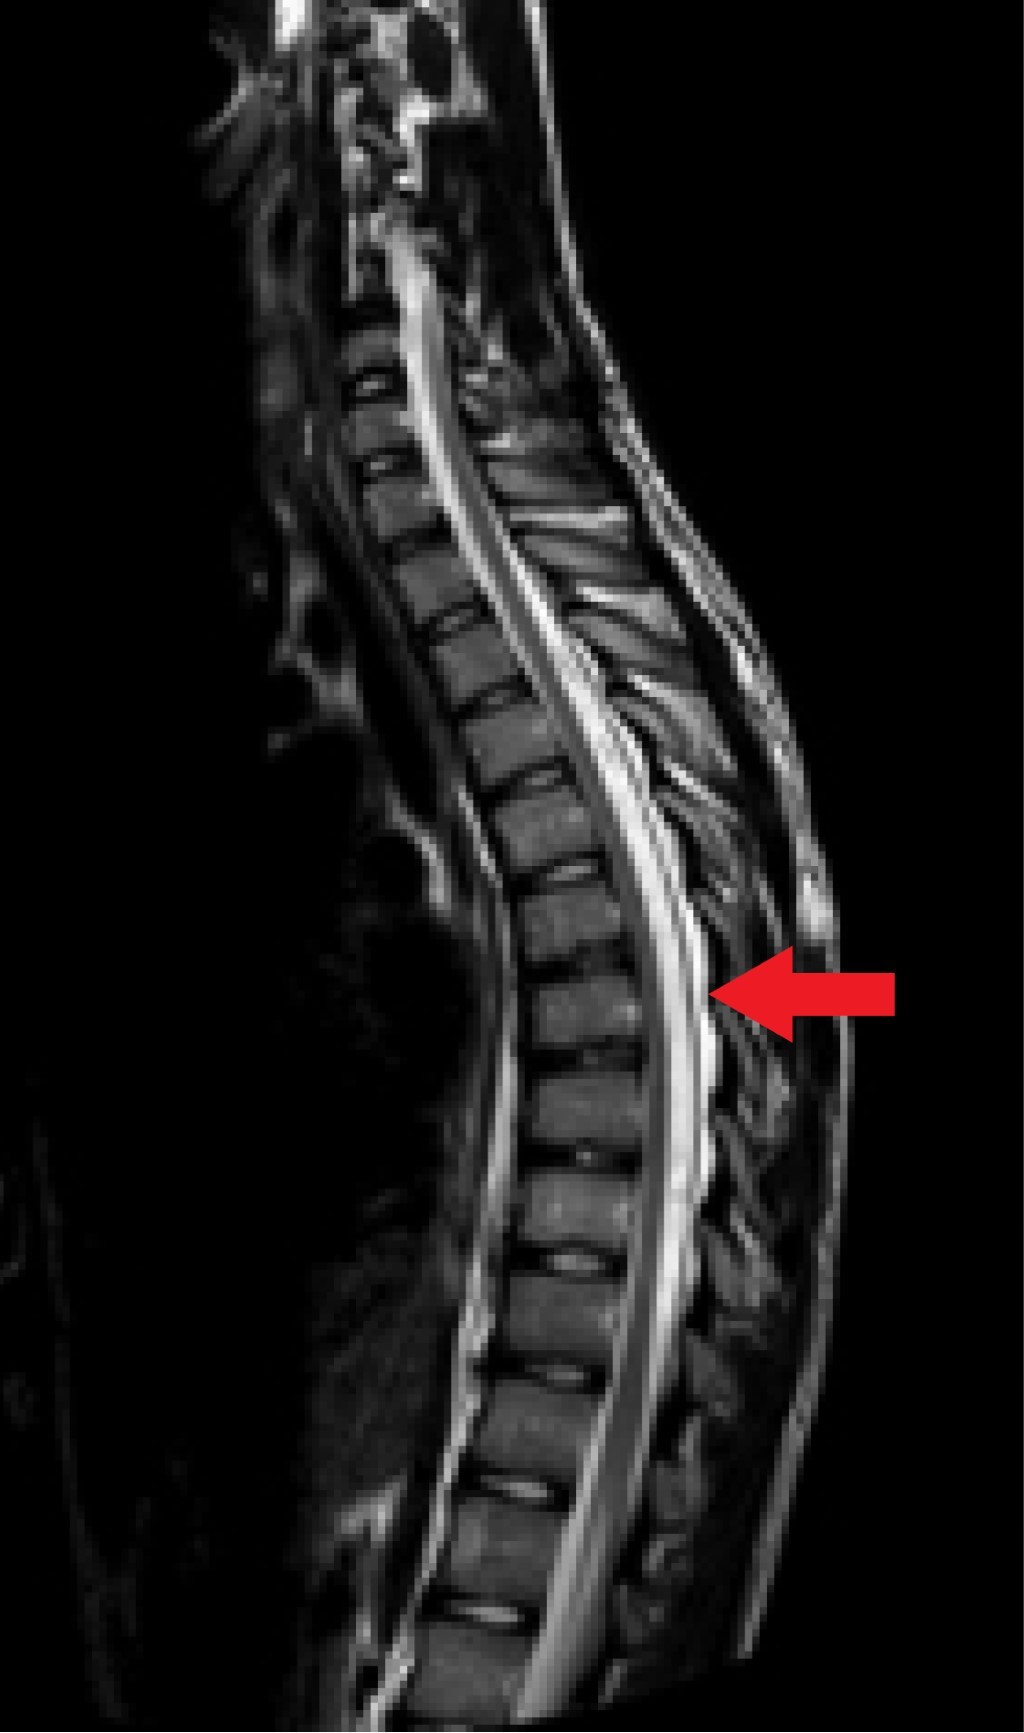

La RM (realizada 20 días después de la segunda consulta) muestra un material hipertenso en las secuencias T1 (Figura 1) y T2 (Figura 2) e hipointenso en la secuencia STIR (Figura 3) en el espacio epidural posterior desde D3 a D9. Con ello se llega al diagnóstico de lipomatosis espinal epidural posterior desde D3 a D9.

El estándar de oro para el diagnóstico de la SEL es la RM ponderada en T1 y las imágenes axiales y sagitales pueden mostrar un aumento de la grasa epidural como una imagen hiperintensa. Las imágenes ponderadas en T2 muestran una intensidad intermedia; la supresión grasa (STIR) es el método de diagnóstico definitivo, mostrando la SEL como una imagen hipointensa.13

Figura 2